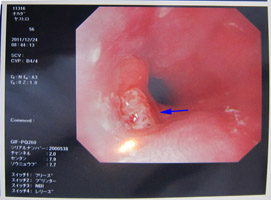

| 内視鏡検査(大腸カメラ) |

がん予備群ポリープ |